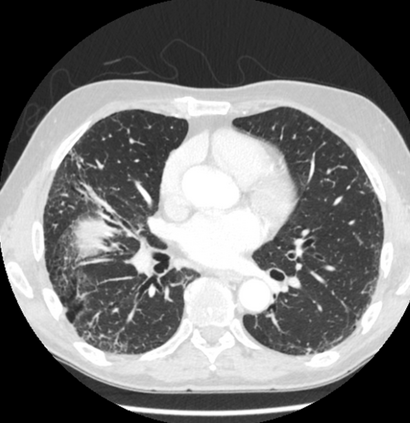

In this study, we aim to initiate the development of Radiology Foundation Model, termed as RadFM.We consider the construction of foundational models from the perspectives of data, model design, and evaluation thoroughly. Our contribution can be concluded as follows: (i), we construct a large-scale Medical Multi-modal Dataset, MedMD, consisting of 16M 2D and 3D medical scans. To the best of our knowledge, this is the first multi-modal dataset containing 3D medical scans. (ii), We propose an architecture that enables visually conditioned generative pre-training, allowing for the integration of text input interleaved with 2D or 3D medical scans to generate response for diverse radiologic tasks. The model was initially pre-trained on MedMD and subsequently domain-specific fine-tuned on RadMD, a radiologic cleaned version of MedMD, containing 3M radiologic visual-language pairs. (iii), we propose a new evaluation benchmark that comprises five tasks, aiming to comprehensively assess the capability of foundation models in handling practical clinical problems. Our experimental results confirm that RadFM significantly outperforms existing multi-modal foundation models. The codes, data, and model checkpoint will all be made publicly available to promote further research and development in the field.